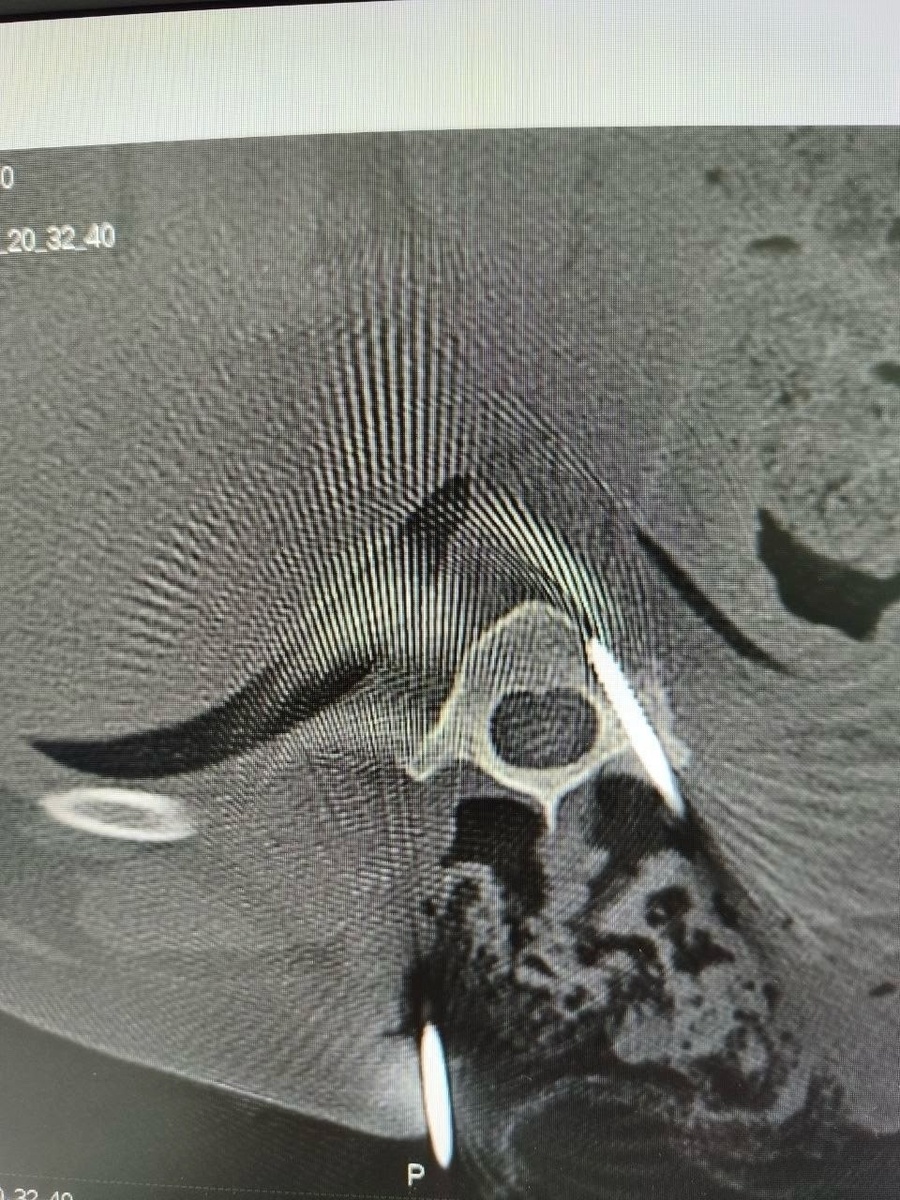

6 апреля у Карандаша отказали задние лапы, и Роман привёз его в Курскую ветклинику на консультацию. После осмотра невролога и КТ была проведена хирургическая стабилизация сегмента позвоночника.